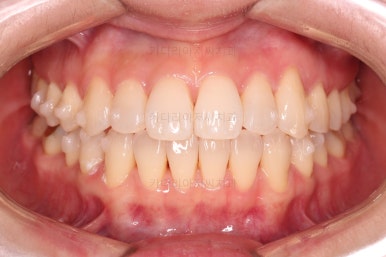

1. 초진

초진 시 입안의 모습입니다.

덧니가 눈에 띄고요.

맞물림이 긴밀하지 못한 상태였습니다.

전반적으로 약간 삐뚤지만 많이 심하다고 보긴 힘들었습니다.